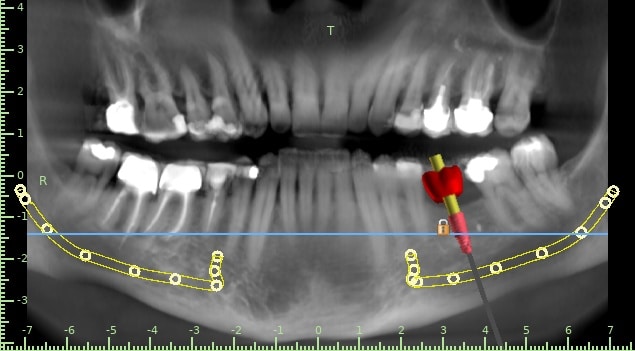

here a guided surgery case where a lower molar was replaces by an implant ,flapless ,thanks to a good digital planification and a realisation of a surgical guide